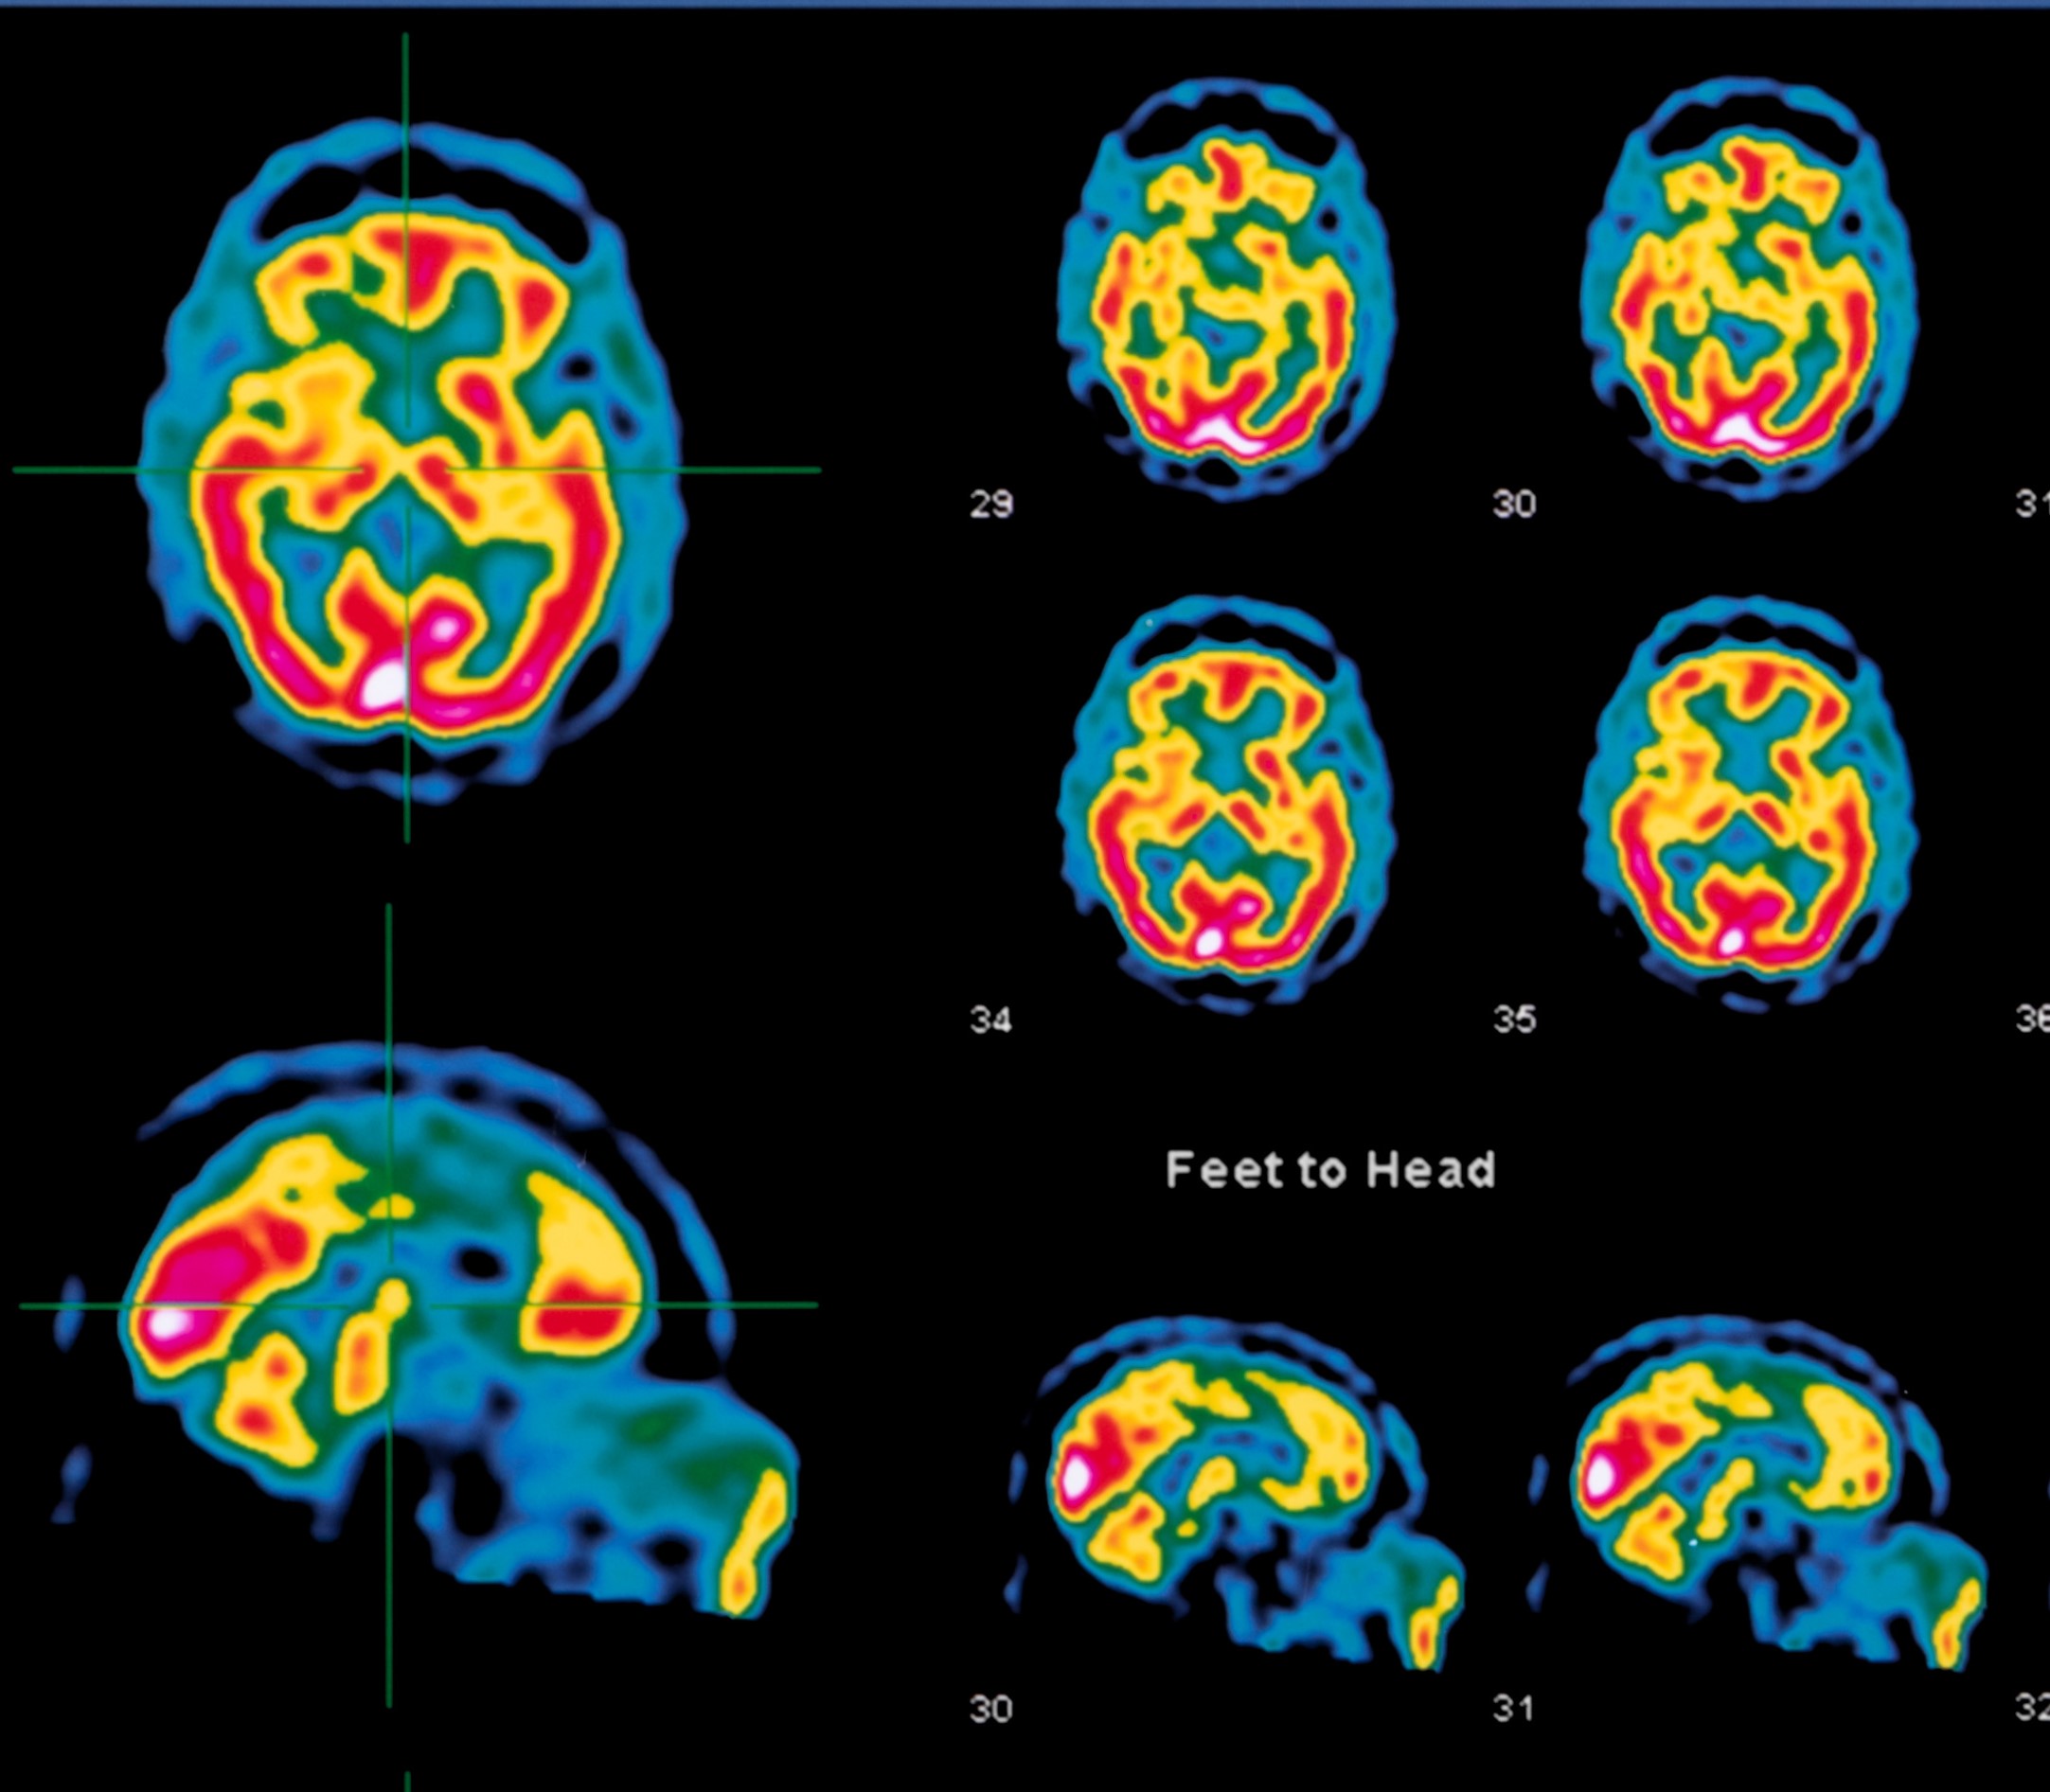

The study analyzed nearly 200,000 brain SPECT scans from tens of thousands of patients at Amen Clinics.

SPECT (single photon emission computed tomography) is a functional brain imaging technology with strong evidence for use in diagnosing dementia, traumatic brain injuries, complex neuropsychiatric issues, treatment-resistant disorders, cerebrovascular disease, and seizures.

In particular, the new study appearing in Frontiers in Psychiatry outlines seven specific clinical applications for brain SPECT imaging that can help identify a wide variety of issues related to psychiatry such as: mood instability, ADHD, cognitive decline, obsessive compulsive disorder, posttraumatic stress disorder (PTSD), substance abuse, exposure to toxins, infections (Lyme disease), traumatic brain injury, and more.